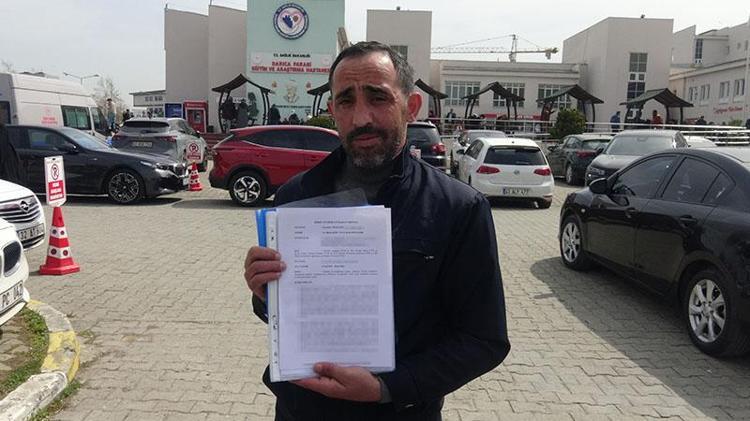

1 SANTİMETRE METAL PARÇA TESPİT EDİLDİ

Nurettin Güleryüz, ampütasyon sonrası sağ kolunda ağrı ve şişlik şikayetleri yaşayınca Darıca Farabi Eğitim ve Araştırma Hastanesi’ne başvurdu. Burada yapılan tetkiklerde, Güleryüz’ün kolunda 14 milimetre boyutunda yabancı cisim bulundu. Marmara Üniversitesi Pendik Eğitim ve Araştırma Hastanesi’nde düzenlenen epikriz formunda ise sağ kol dirsek üzerinde yaklaşık 1 santimetre metal parçaya rastlandığı belirtildi. 9 aydır çalışamadığını belirten Nurettin Güleryüz, iki özel hastane hakkında avukatı aracılığıyla savcılığa suç duyurusunda bulundu. Öte yandan Güleryüz’ün, kolunda tespit edilen metal cismin çıkarılması için Darıca Farabi Eğitim ve Araştırma Hastanesi’nde ameliyata alınacak.

Yetkililerden yardım beklediğini dile getiren Güleryüz, “Hastanenin ihmalleri nedeniyle parmağımı kaybettim. 2 defa ameliyat oldum, herhangi bir röntgen ve MR çekimi yapılmadı. Doktora söylediğimiz halde bizi hiçbir şekilde dinlemedi. Bize, ‘İyiye gidiyor’ dedi en sonunda parmağım komple geriye döndü. Parmağımda ve elime çürümeler başladı. Ampute olmadan önce kolumda ağrılar vardı. Doktora ‘Hocam bileğime doğru ağrılarım var’ dedim. Beni dinlemediler. Sonrasında kolumda metal kaldığını öğrendim. İhmal olduğunu düşünüyorum. Kesinlikle ihmal, kola demir nasıl girebilir. 9 aydır çalışamıyorum. Yüzde 46 engelliyken, yüzde 75 engelli oldum. Çalışamıyorum emeklilik dilekçesi verdim, o da daha gelmedi. Bu konuda çok mağdurum. Savcılığa suç duyurusunda bulundum. 9 ay oldu henüz soruşturma izni gelmedi. Açılan bir davamız yok, yetkililerden destek istiyorum” diye konuştu.